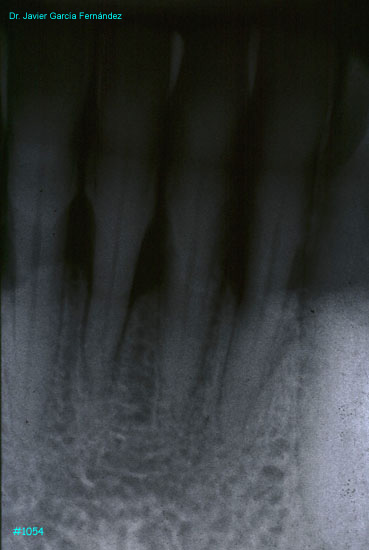

Atlas of Surgical Techniques in Periodontics. Chapter III. Atlas de Técnicas Quirúrgicas en Periodoncia